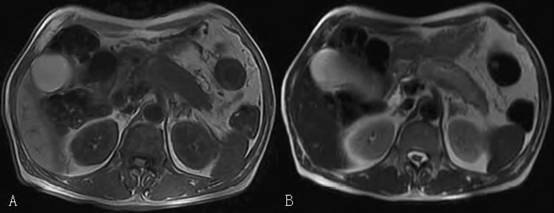

注: A 为T1 信号,B 为T2 信号; 见胰体尾部强化幅度明显减弱,呈轻度持续缓慢强化,呈明显低信号,病变区域胰腺周围见包膜样明显强化,局部胰腺呈腊肠样改变,胰尾部见小串珠状扩张胰管

上腹部MRI/MRCP检查结果

上腹部MRI 示胰腺增大,胰头信号大致正常,胰体尾部信号异常,T2 信号稍高,T1 等信号,增强后胰头实质强化均匀,胰体尾部强化幅度明显减弱,呈轻度持续缓慢强化,呈明显低信号,病变区域胰腺周围见包膜样明显强化,局部胰腺呈腊肠样改变,胰尾部见小串珠状扩张胰管,余区域胰管未见扩张。

磁共振胰胆管造影( MRCP)示肝内外胆管走行、分布未见明显异常,肝内外胆管未见明显扩张及狭窄; 胰尾部分支胰管见小串珠状稍扩张,余胰管未见扩张。

影像学诊断: 胰腺改变,炎症性病变可能性大,AIP 可能性大; 肠系膜上静脉近心端及脾静脉闭塞可能; 胰尾部胰管轻微扩张,建议密切随访。